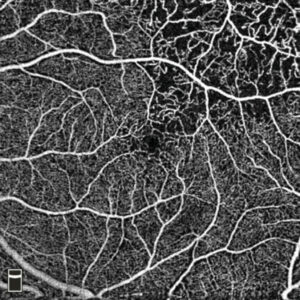

Optical Coherence Tomography and Angiography

OCT and OCT-A provide high-resolution structural scans of the retina, retinal vessels, nerve layer thickness, and the optic nerve itself. These pictures and analytic data help your doctor determine if you have early signs of macular degeneration or glaucoma, and also if you have any blood vessel deficits in the eye from diabetes, mini- strokes. Analysis of the retinal neural and vascular tissue is also helpful in the early detection of Alzheimer’s disease and Parkinson’s disease.